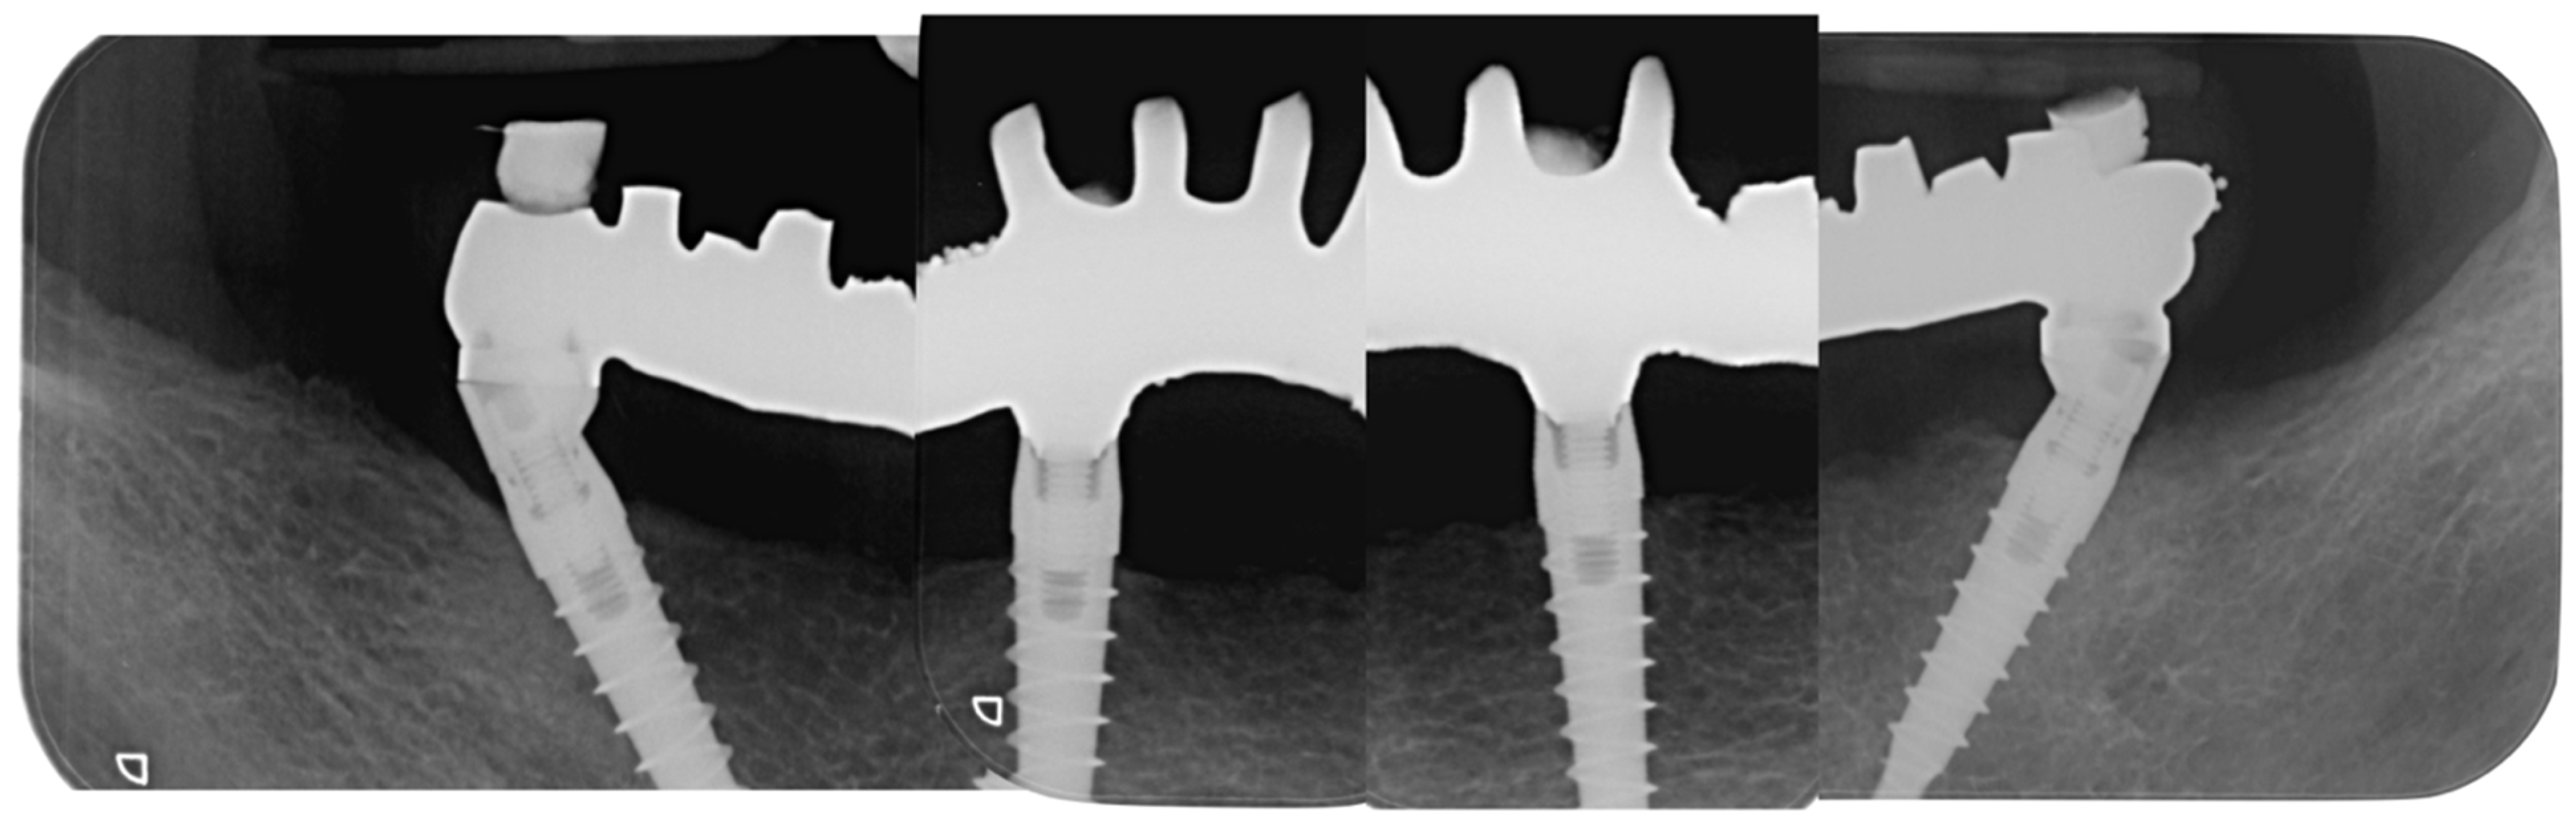

2. Case Report

3. Results